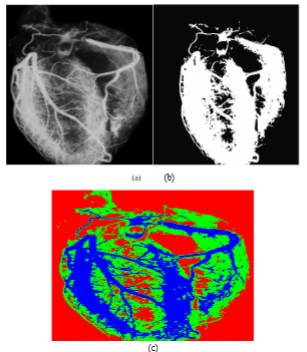

Studies have proven that the blockage that may occur in the blood vessels is a direct cause of cardiac arrest and myocardial arrest, so it is necessary to use the results of the application of radiological examination methods of the heart and large blood vessels - X-ray images, ultrasound, MRI. Therefore, the paper proposed a segmentation method based on a new approach to calculating a continuous and accurate membership function using the (Heaviside and Polynomials) function, in order to extract distinct regions in the images, making the analysis process effective and obtaining an accurate diagnosis, as the results proved that the proposed method highlights the important parts of the cardiovascular images more clearly compared to by traditional methods.